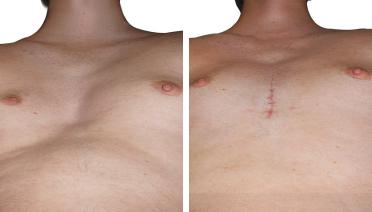

La tecnica di impianto su misura è una tecnica chirurgica minore che consiste nel riempire la concavità creata dal Pectus con un impianto personalizzato. Si tratta di un intervento rapido, a basso rischio, con un risultato immediato e una breve convalescenza.

In questa pagina, troverà i risultati di questa operazione a seconda del tipo di Pectus : mediale, asimmetrico, più o meno profondo o lungo.

Tipo 2 : Ampio, poco profondo e simmetrico,